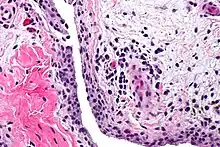

| Chronic synovitis | |

Synovitis is the medical term for inflammation of the synovial membrane. This membrane lines joints that possess cavities, known as synovial joints. The condition is usually painful, particularly when the joint is moved. The joint usually swells due to synovial fluid collection.